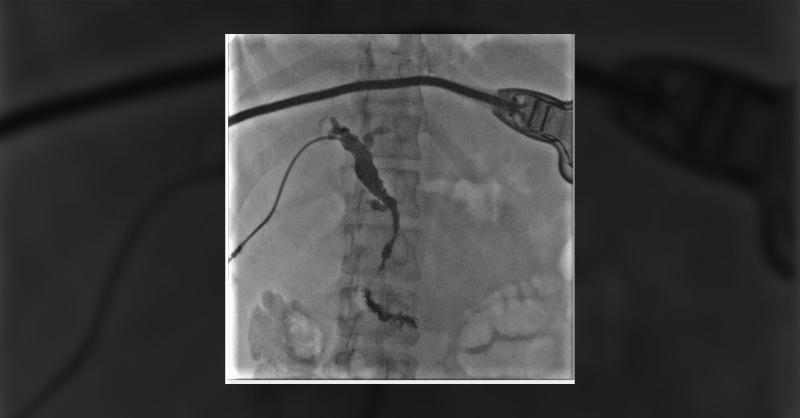

A 36-year-old presented with abdominal pain, nausea, and vomiting. Upon physical examination, scleral icterus and abdominal tenderness were noted. Lab tests revealed high lipase levels and abnormal liver function. Initial results indicated lipase of 4,693 U/L, total bilirubin of 12.3 mg/dL, direct bilirubin of 9.47 mg/dL, alkaline phosphatase of 88